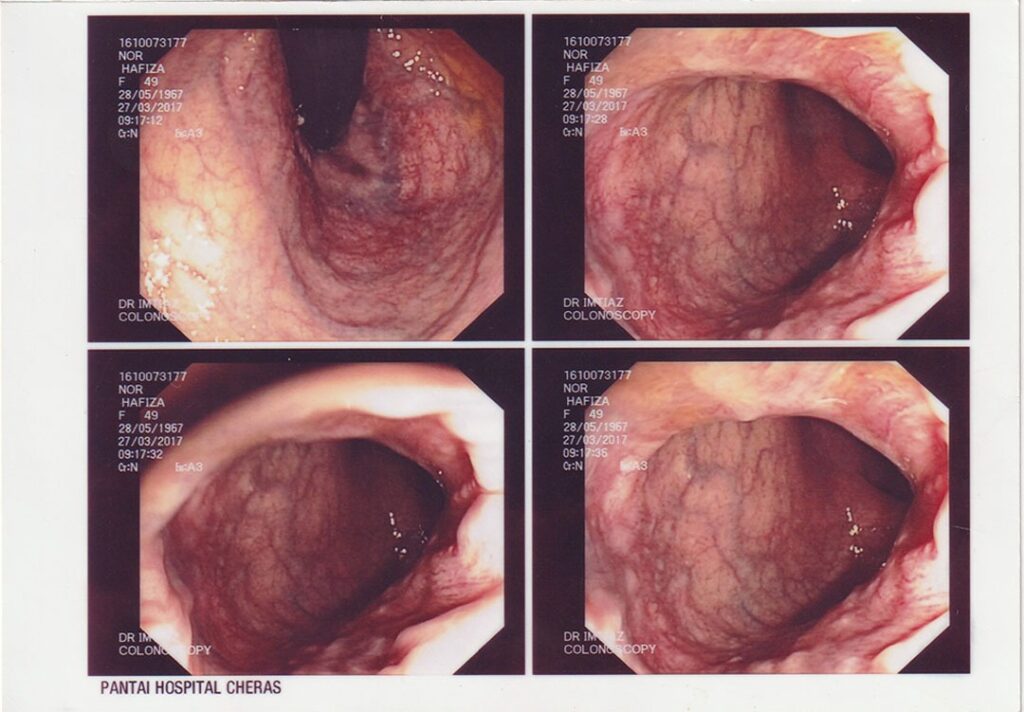

Perjalanan Kesejahteraan Dalaman & Sistem Pencernaan

54 Tahun, Kajang, Selangor

"SISTEM YANG DAHULUNYA ROSAK, KINI TELAH KEMBALI KEPADA FITRAH ASALNYA."

Pada tahun 2016, saya mula mengalami ketidakselesaan yang teruk pada bahagian perut, pergerakan usus yang tidak teratur, dan gejala membimbangkan yang mengganggu kehidupan seharian. Apabila menerima diagnosis serius mengenai kesihatan sistem pencernaan saya, dunia terasa gelap seketika. Saya bimbangkan masa depan suami dan anak-anak. Alhamdulillah, suami saya terjumpa risalah Ibnu Sina Wellness™ di surau dan mencadangkan agar saya mencubanya sebagai jalan sokongan ke arah pemulihan.

Saya memulakan perjalanan bersama Ibnu Sina Wellness™ pada Januari 2017 dengan penuh harapan. Hasilnya sungguh luar biasa! Dalam tempoh beberapa bulan, pemeriksaan menunjukkan sistem dalaman saya beransur-ansur pulih dengan sendirinya. Menjelang 2018, pemerhatian klinikal menunjukkan saluran pencernaan saya telah kembali ke tahap yang sangat sihat dan cergas. Pendekatan ini bukan sahaja menyokong pemulihan fizikal, malah menguatkan kesejahteraan emosi dan spiritual saya.